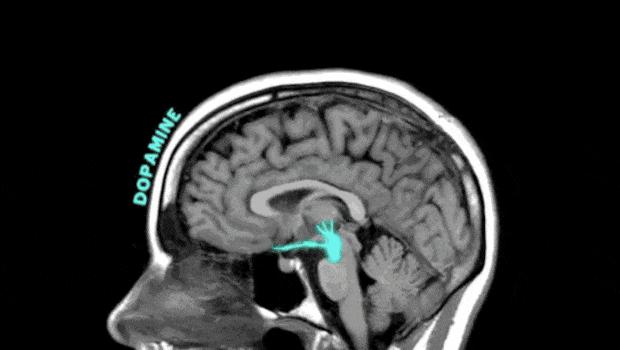

靠奶茶、蛋糕等來緩解情緒,其實是藉助血糖快速上升,刺激多巴胺短暫釋放,從而獲取即時快感。所以情緒管理能力較差的人,會簡單粗暴地通過食物來抑制或緩解負面情緒。